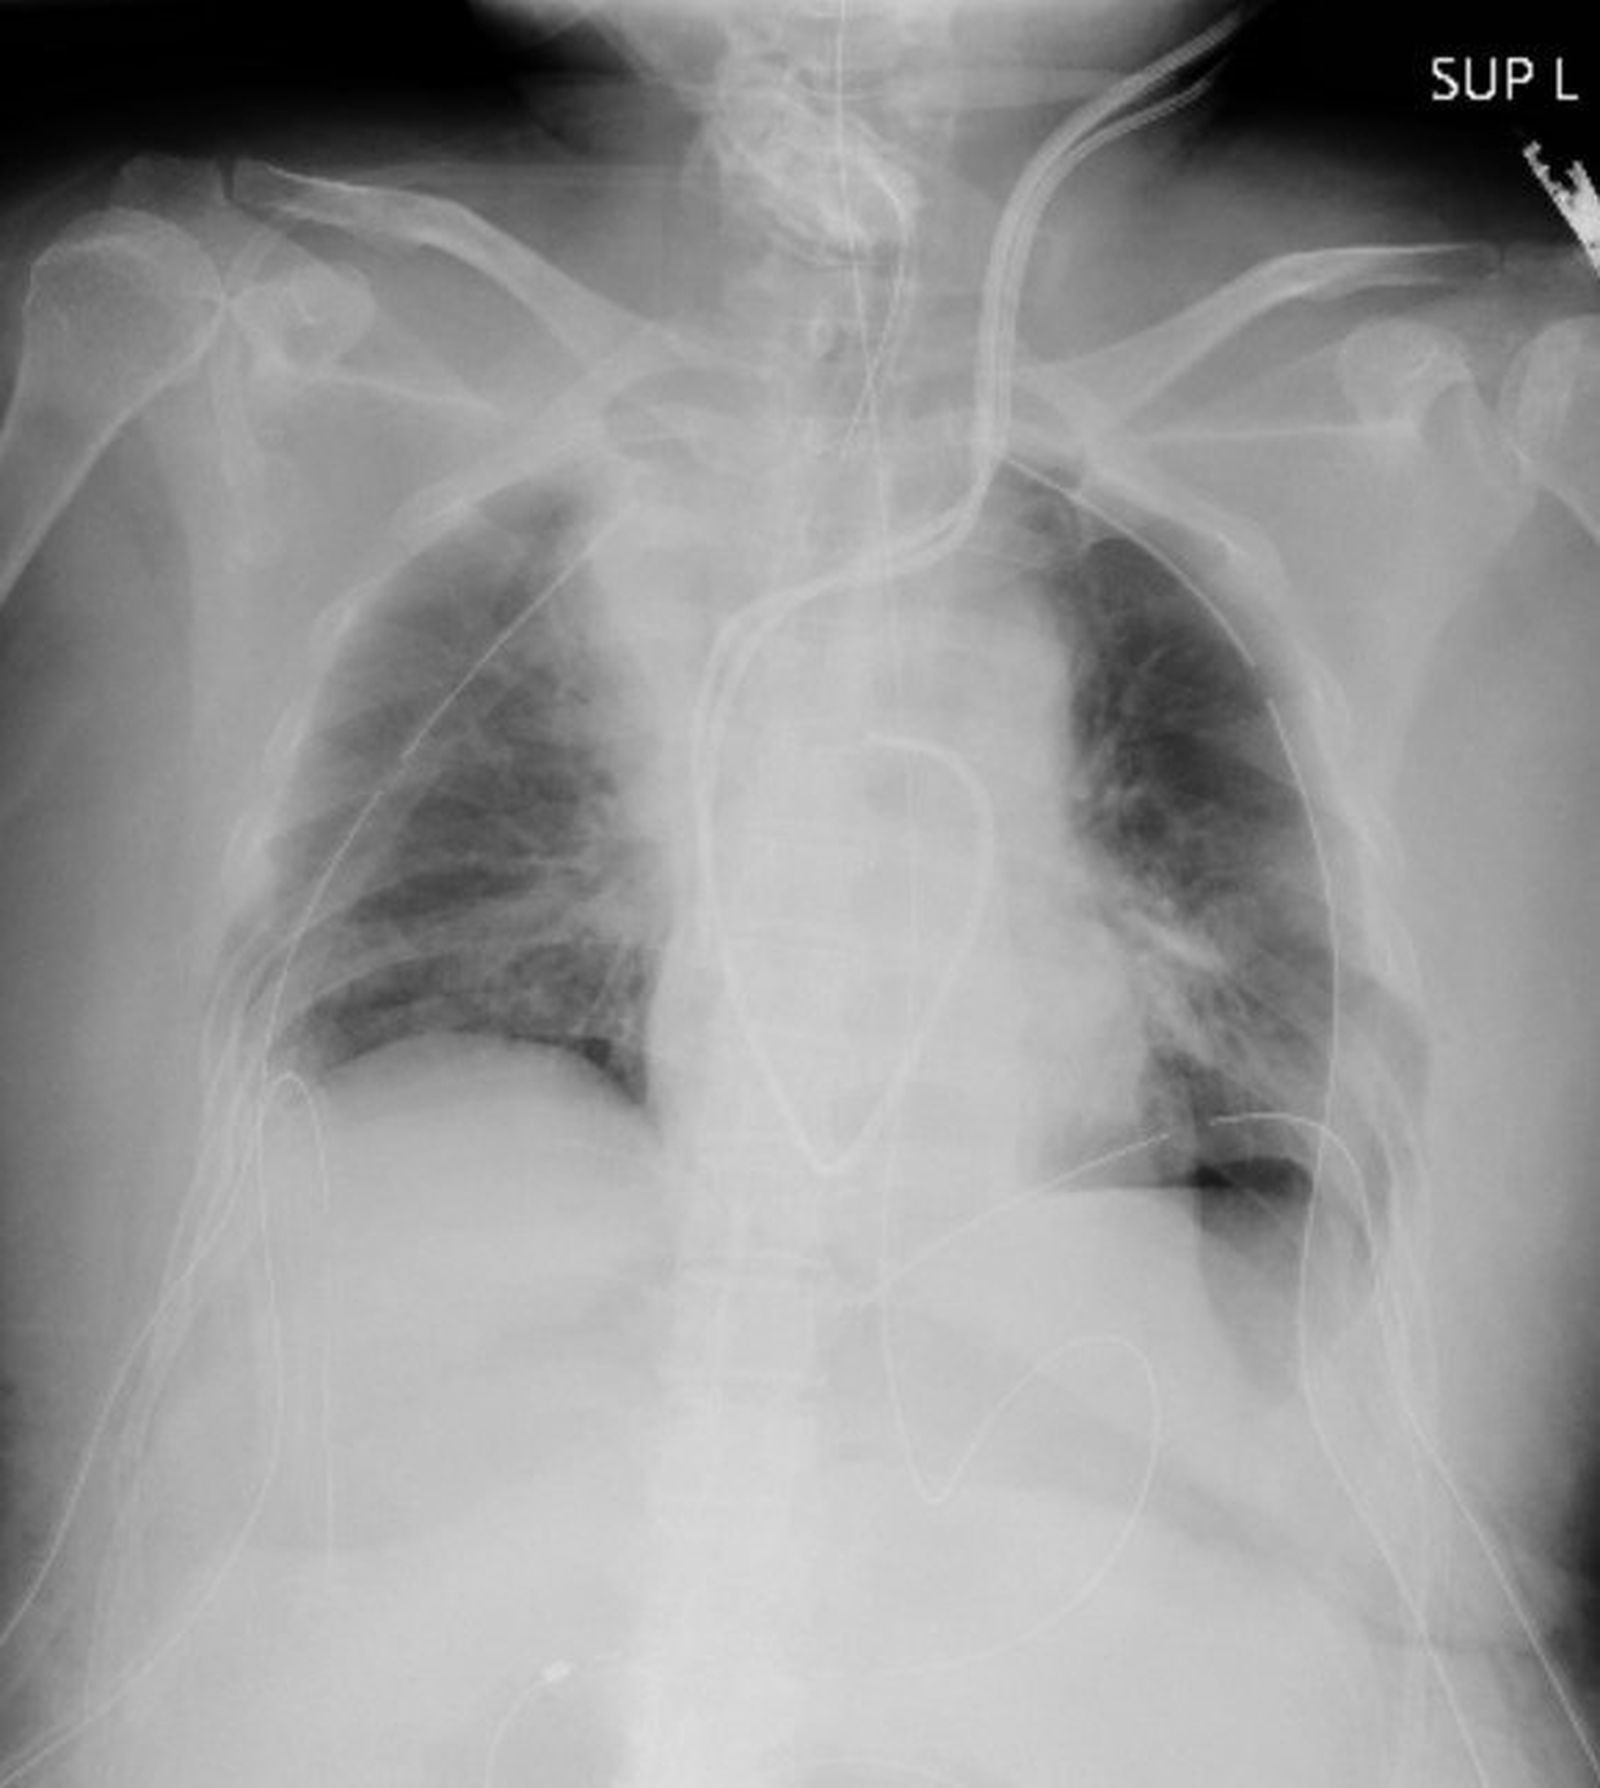

Radiografía pulmonar de la primera paciente del mundo en recibir un trasplante de pulmón desde pacientes vivos.

Radiografía pulmonar de la primera paciente del mundo en recibir un trasplante de pulmón desde pacientes vivos. / Kyoto University Hospital